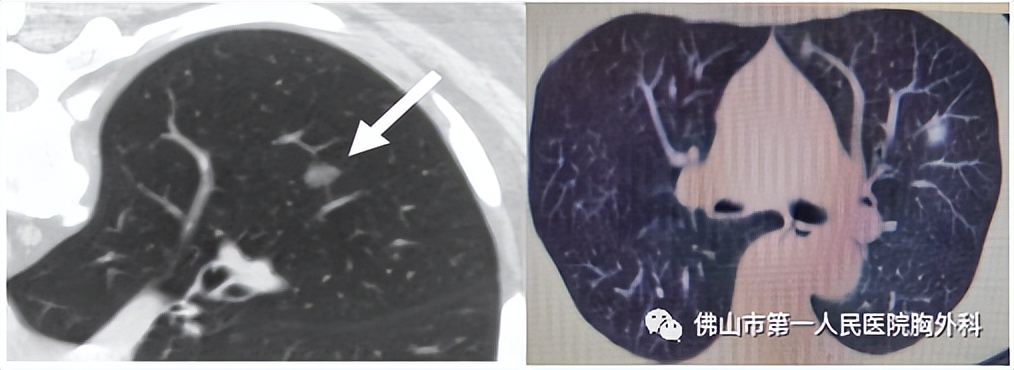

那么体检时胸部CT发现了肺结节怎么办?佛山市第一人民医院首席专家、胸外科杨劼主任医师告诉大家:体检CT发现肺结节和肺磨玻璃结节,没必要过分紧张。胸部CT检查普及出现一个新的概念,一般影像学上表现把3cm以上称为肿块,3cm以下称为结节,1cm以下称为小结节,0.5cm以下称为微结节。肺结节依据其密度不同又可分为实性结节、部分实性结节、磨玻璃结节。磨玻璃结节是影像学上的一种描述,一般指的是肺内可见密度增高类圆形局限的阴影,指的是密度像一层磨砂玻璃样的一种密度,因此叫做磨玻璃结节。磨玻璃属于是似乎能看见,但又看不清楚的一种状态。肺磨玻璃结节可以是炎性增殖、结核,肉芽肿和早期癌症,80%以上是良性的。体检胸部CT发现了肺结节可以先找胸外科或呼吸与肺结节中心、肿瘤内科医师先看看片子评估一下,定期随访复查或微创手术治疗。